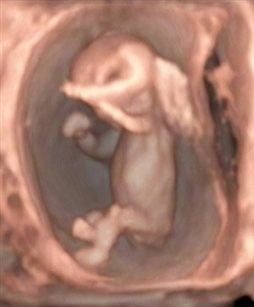

早孕期胎儿颈项透明层(nuchal translusancy thickness,NT)实际上就是宝宝的颈后透明层检查。胎儿畸形与NT值增厚关系密切,当NT的厚度超过正常范围,且数值越大,胎儿出生后患病的几率也越大。除了胎儿出生后,可能会患有染色体、心脏等问题外,还要考虑是否患有唐氏综合征,并要做好进一步检查的准备。

NT检查在孕11~14周做,过了14周,过多的液体可能就会被宝宝正在发育的淋巴系统吸收,准确率就会大大降低。